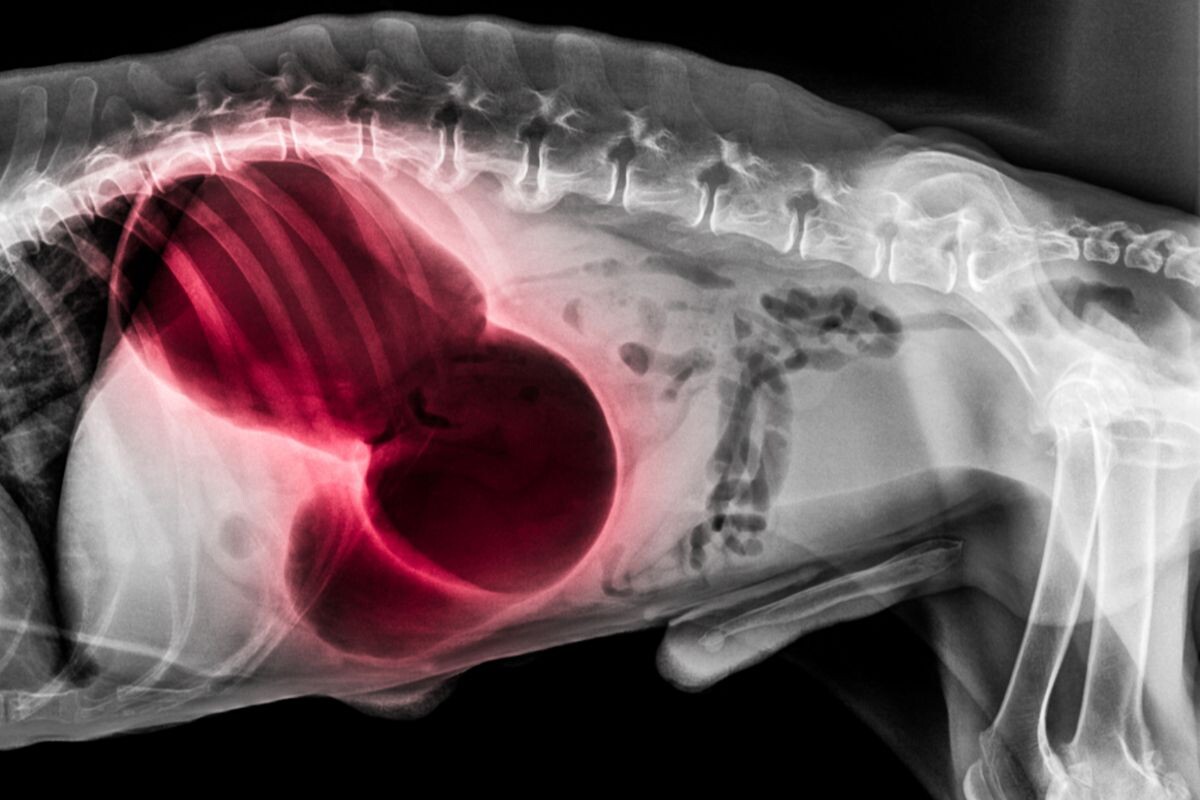

• Рентгенография брюшной полости — это основной метод диагностики заворота желудка. На рентгеновском снимке обычно заметен так называемый симптом двойной пуговицы — раздвоенная полость желудка из-за перекручивания.

Рентгенограмма собаки в боковой проекции, красное выделение при завороте желудка с дилатацией — скручивание желудка...